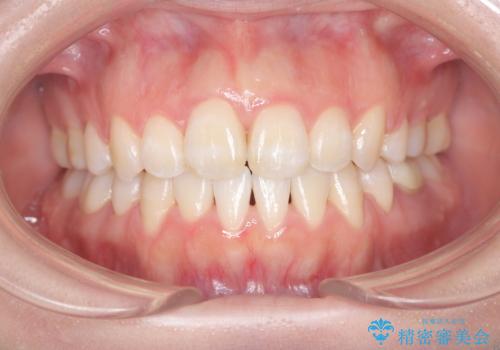

前歯のデコボコと深い咬み合わせを解消